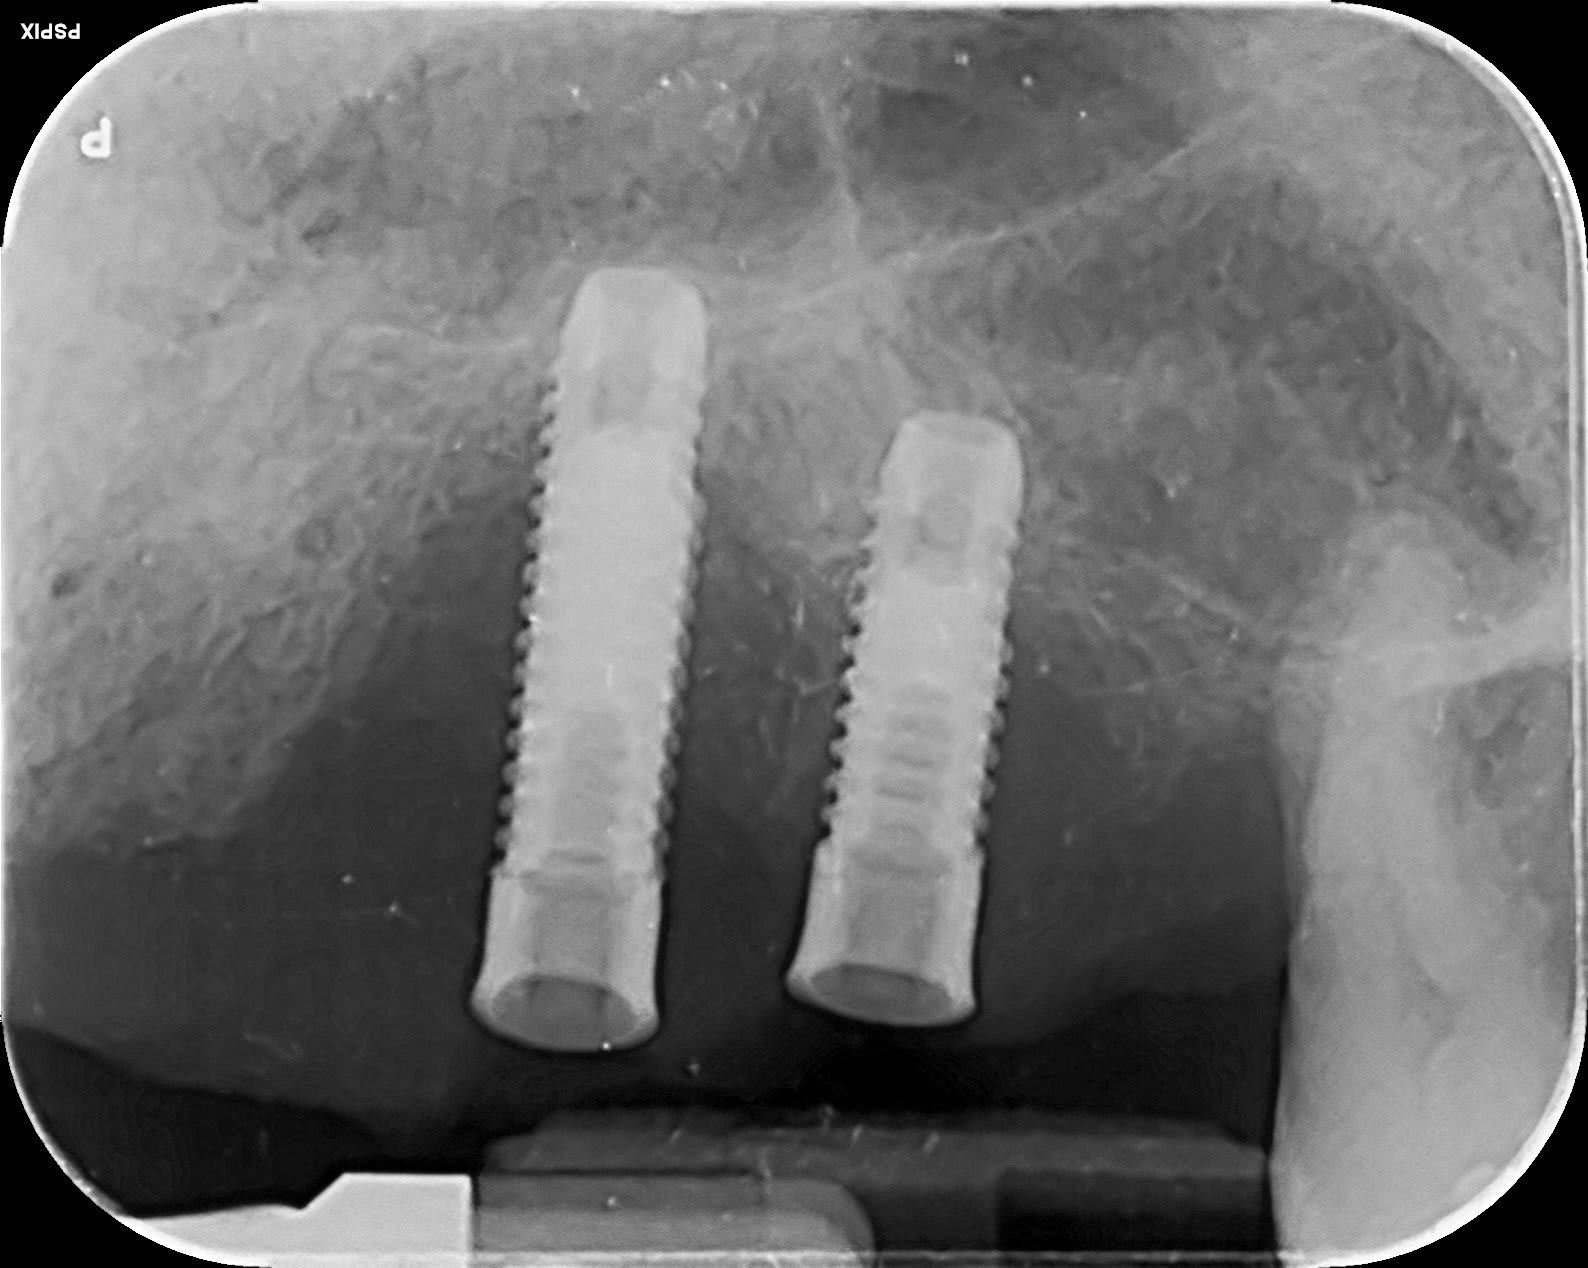

Si une âme charitable pouvoir m'aider sur de l'identification implantaire afin de temporiser avant extraction.

Photo pluton1b h9n4ea - Eugenol

rien trouvé encore.....mais vu l'état.....=> bassinet.....